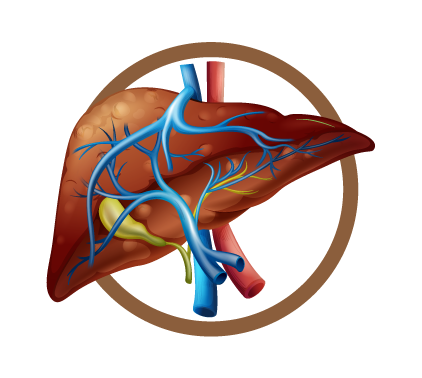

Causas del Hígado graso

Se conocía, por lo general que los hombres que consumían bebidas alcohólicas de forma recurrente sufrían a largo plazo de cirrosis. Sin embargo, en los últimos años es muy común en las citas médicas, ver mujeres con cirrosis por causa del hígado graso.

Incluso, muchas de ellas nunca han consumido bebidas alcohólicas. Hasta los niños menores de 12 años presentan esteatosis hepática.

El Dr. Mike Chang menciona sobre este asunto: “Alguna vez escuché decir a una señora que los niños entre más gorditos están más sanos y entre más flaquitos más enfermo. Es mentira, porque a veces los llenan de colesterol, triglicéridos y su hígado se vuelve grasoso. En esta enfermedad no hay prevalencia de género, ni edad”.

El diagnostica el grado de hígado graso a través de una ecografía, también lo relaciona con los síntomas que presenta el cuerpo. Por ejemplo, si al comer sientes malestares estomacales, diarreas esporádicas, dolor abdominal, picazón al cuerpo o escamas en las manos.

Se asocian los síntomas con los resultados de las enzimas hepáticas. En el cuarto grado el hígado comienza a tener estructuras que se comienzan a dañar, y termina secándose en forma de pasa.

El hígado produce hormonas, defensas, vitamina k. Por eso, es tan importante hacer una buena prevención, porque no existe mejor medicamento que la prevención.

El hígado graso si es reversible, la cirrosis no.